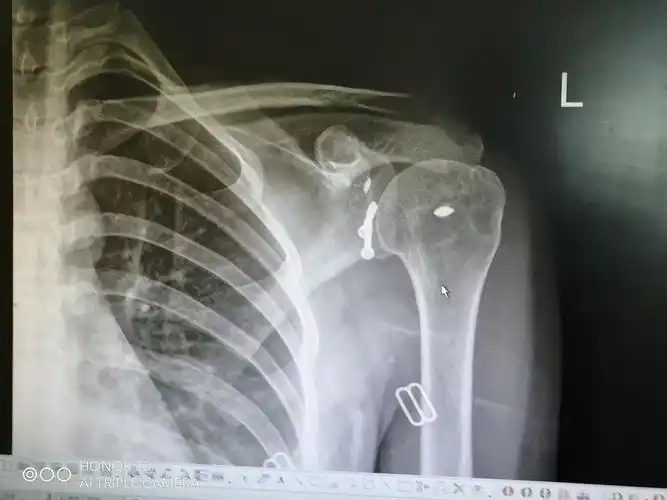

肩盂骨折